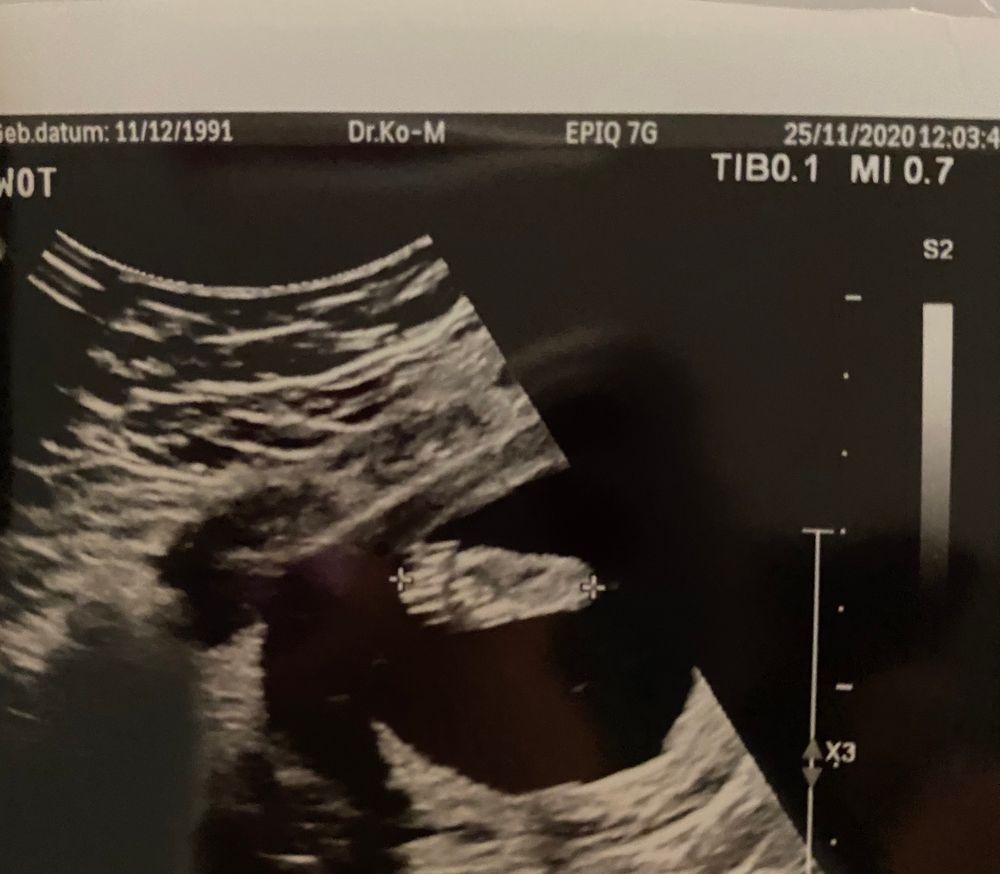

УЗИ, КТГ, доплер18 недель .

Вот на первой фотке вижу пирожок,а на второй бугорок 🤷♀️ Это обе фотки между ножек.

Вес -230 грамм,рост 18 см. Лежит поперёк,я и чувствую удары ножкой всегда слева. Вот и сама ножка ,2.30 см😂